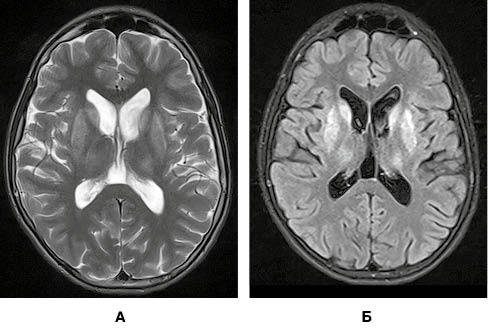

вгоруОсновними ознаками гепатоцеребральної дегенерації, які дозволяє виявити дослідження головного мозку за методом магнітно-резонансної томографії (МРТ), є зміни в базальних ядрах та стовбурі. Головні з них — це підвищення МР-сигналу за режимів Т2 та Т2/Flair від головок хвостатих ядер, блідих куль, лушпин та таламусів (рис. 1).

При виконання МРТ-дослідження головного мозку пацієнта виявлено типові ознаки хвороби Вільсона у вигляді підвищення МР-сигналу від головок хвостатих ядер, лушпин, блідих куль та таламусів в режимах Т2/Flair і Т2. Також наявне підвищення сигналу від покришки середнього мозку й дорзальних відділів моста (рис. 3).